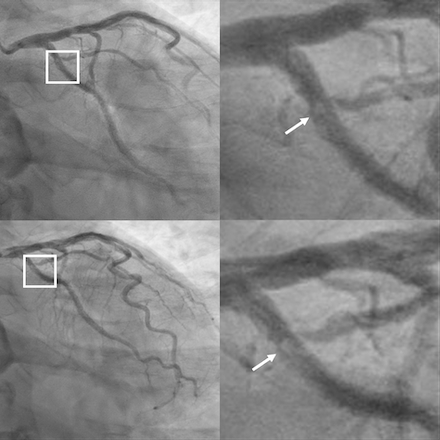

One week later, he developed acute epigastric pain and hypotension requiring vasopressors. Despite triple therapy (aspirin, prasugrel, apixaban), ECG indicated lateral STEMI (Figure 1B). Repeated CAG showed a new thrombus in the proximal LCx stents though there was TIMI 3 flow (Figure 3). Aspiration thrombectomy with 2 additional DES were placed. Right heart catheterization revealed mixed cardiogenic and vasoplegic shock, most likely from metabolic acidosis and uremia. A temporary ventricular support device was inserted, and CRRT was started. Repeated echocardiogram showed EF 30%. Patient subsequently developed DIC and multiorgan failure. Despite maximal support, he developed coffee ground emesis which was likely aspirated leading to PEA cardiac arrest.